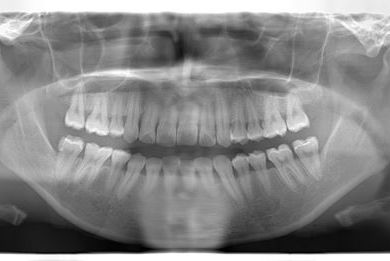

治療後

• 治療後

治療内容 ハイブリッドセラミックインレー3本

治療部位

7 6 7

総治療費 113,715円

治療期間 2ヶ月